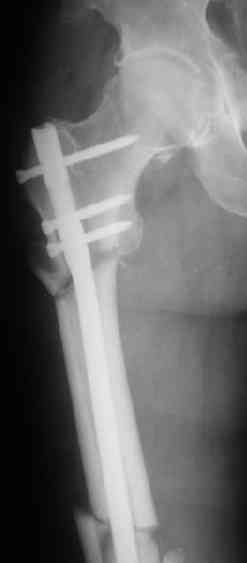

> денамизация - февраль 2006. ( 3 и 4 снимки) на сегодняшний день (снимок 5) беспокоит боли в тбс...

Учитывая точку введения - верхушка б\вертела - что бы исправить варус взял бы соответствующий гвоздь: длинную Гамму или PFN или Recon

Судя по уровню перелома, винты в шейку избыточны, подойдет и диафизарный гвоздь. Все, что нужно, это тиски и труба. Загнуть сразу ниже отверстий градусов на 8-10, и вся недолга. Последние годы у нас это рутинная практика. Предызогнутые еще с завода гвозди неудобны тем, что они уже правый-левый.

Согласен, что закрытый реостеосинтез с рассверливанием и коррекцией оси - это то, что надо. Мы бы ввели в центральный отломок статических 2-3 винта, и один динамический винт в дистальном отломке.